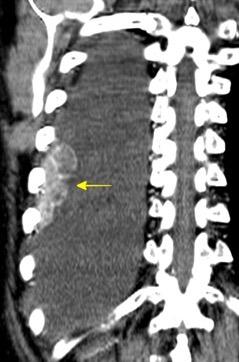

63. HEMOTÓRAX. ANEURISMA ASI ROTO.

Rotura de aneurisma de arteria subclavia Aneurisma “deshinchado” Hemotórax

Fallece en el acto de tomar esta radiografía. La mayoría ateroescleróticos. Más frecuente a la derecha.La rotura: 32-47% de las muertes.